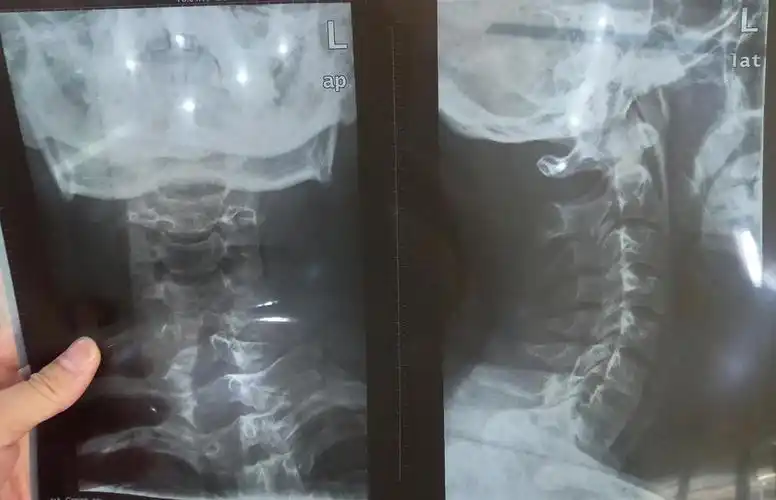

脊柱侧弯,颈椎侧弯,怕是没救了